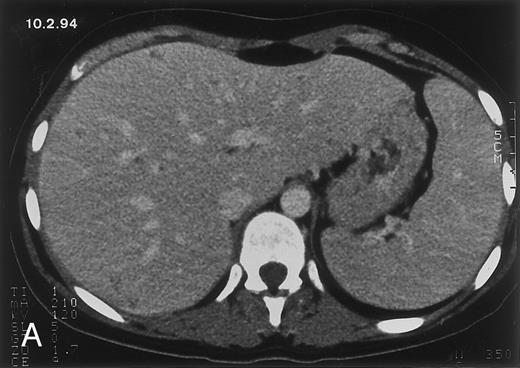

Radiologic evolution in patient B. (A) Postcontrast abdominal CT scan on February 10, 1994 shows multiple small hypodense areas in all segments of the liver suggestive of hepatic candidiasis. Twenty-four days previously, the patient had recovered from severe neutropenia after the second cycle of chemotherapy for ALL. (B) On May 4, 16 days after the neutrophil count had dropped below 500/μL in the third chemotherapy cycle, there is clear improvement of the radiologic findings, with only a few hypodense areas in the liver.